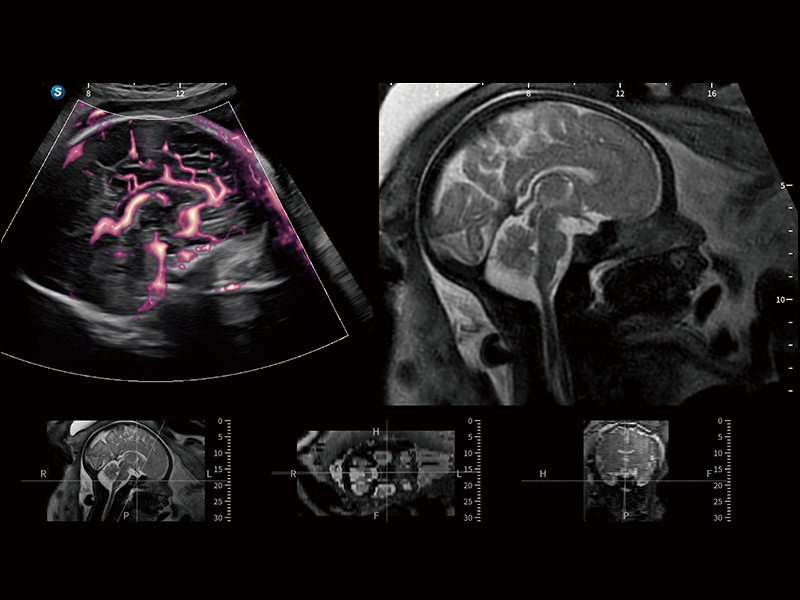

胎兒顱腦融合